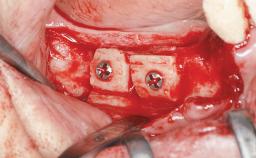

Ridge Preservation and Implant Placement for a Fixed Dental Prosthesis After a Car Accident

It is well known to clinicians that any removal of teeth will, over time, cause the dimensions of the alveolar ridge to be reduced by resorption of the bundle bone and by changes related to external modeling. This development is particularly evident in the crestal region with its thin buccal bone that consists of bundle bone almost entirely. The facial bone will rapidly resorb as blood supply from the periodontal ligament gets disrupted (Araújo and Lindhe 2005). There is no reason why traumatic tooth loss should not have the same consequences. It takes more than achieving implant osseointegration for a treatment outcome to be considered successful. No deficiency of bone or soft tissue is acceptable when an ideal esthetic outcome is the goal. Several articles (Sanz and coworkers 2011; Vignoletti and coworkers 2011) have reported on techniques of improving the alveolar ridge for implant treatment, notably focusing on protecting tissues from resorption.

Bone Augmentation Horizontal|Simultaneous|Sinus Floor Elevation|Staged

Augmentation Materials Xenogenous|Membrane